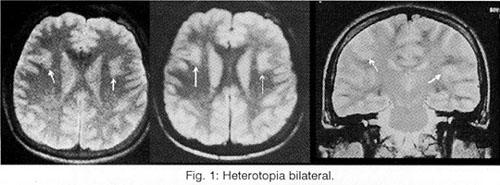

But the most important task of the Neuroimaging is (always in connection to the clinic) the help to the localisation of the lesions (which provoke the epileptic seizures), to the differential diagnosis of this lesion among hereditary illnesses (phacomatoses, leukodystrophies), abnormalities of development (dysplasias, vascular malformations, neuronal migration disorders: heterotopia-double cortex syndrome (Fig. 1), schizencephaly, lissencephaly, unilateral Megalencephaly), perinatal cerebral injuries (between the 30th week of pregnancy and the end of the first month of life due to placental insufficiency, hypoxia, infections, intoxication and mechanical birth trauma4, presented as porencephaly, focal or generalized enlargement of the ventricular system or the subarachnoid space (Fig. 2), hippocampal sclerosis (Fig. 3 and 4) or acquired lesions (benign or malign neoplasms, cerebrovascular diseases, encephalitis (Fig. 5), cerebral abscess, parasitic, fungal and protozoan diseases (Fig. 6), cerebrocranial injuries, degenerative diseases), for the best coping with the patient's problem (conventional pharmaceutical or neurosurgical treatment), as well as for the prognosis before and after the preferred therapy.